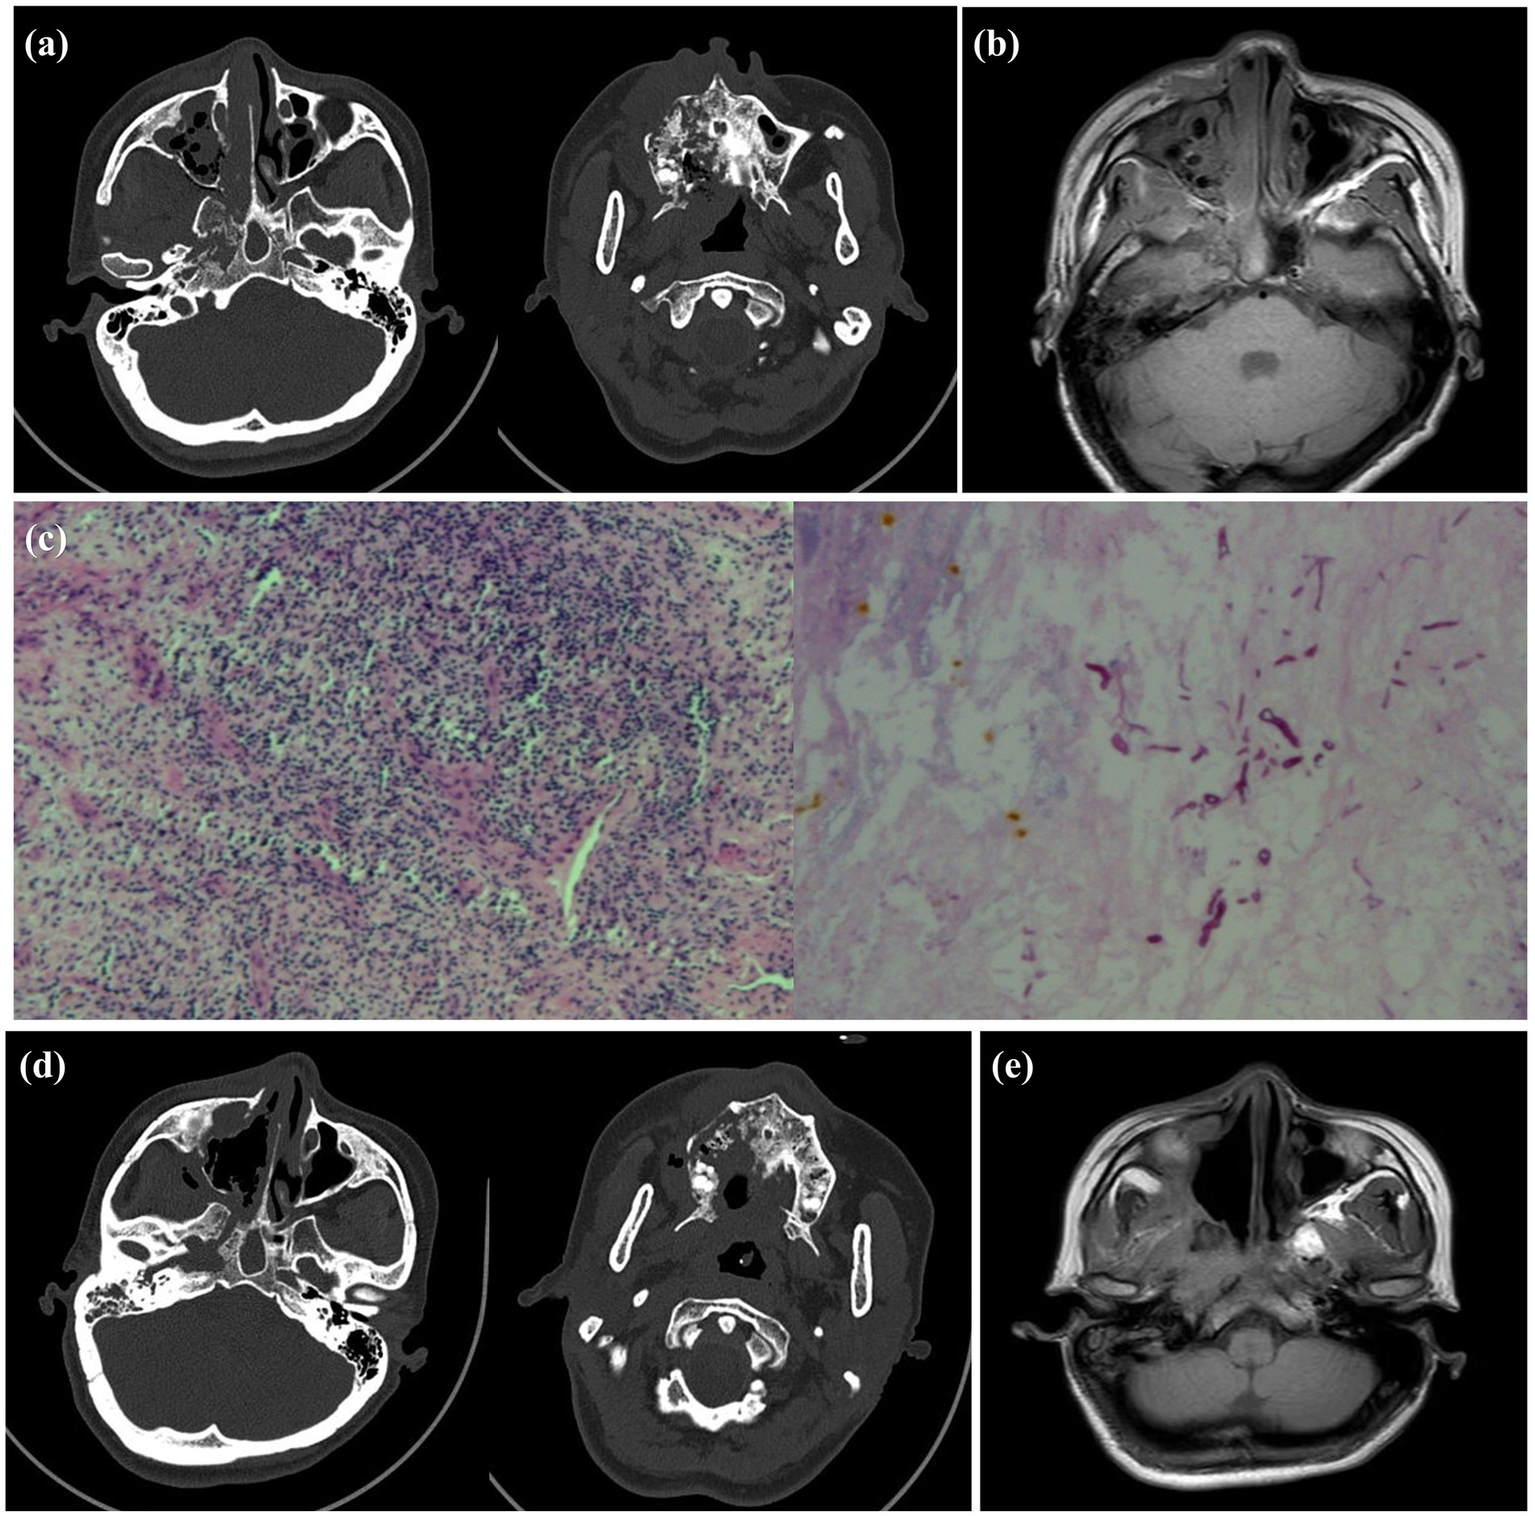

Figure 2

Preoperative and postoperative imaging examination and intraoperative pathology of the patient. (a) Preoperative sinus CT showed worm-like bone destruction on the right side. (b) Preoperative MRI showed a large amount of necrotic tissue in the right nasal cavity. (c) Intraoperative pathology confirmed the presence of Mucor hyphae, preoperative MRI revealed extensive necrotic tissue in the right nasal cavity. (d) Postoperative CT review indicated that dead bone was almost completely removed. (e) Two months after the second surgery, MRI showed recovery was good, with inflammatory soft tissue nearly resolved.

Following preoperative evaluation, the patient underwent endoscopic nasal surgery and intraoperative biopsy. Histopathological examination of frozen sections revealed extensive inflammatory necrosis and suppurative exudate, with visible mucor clusters. Special staining showed PAS (+) (Figure 2c). Given the absence of skull base invasion, extensive debridement was performed. Due to the risks associated with complete debridement in a single operation, two staged procedures were planned. For the first operation, we adopted the right nasal cavity and paranasal sinus lesion resection under nasal endoscopy, total paranasal sinus opening, orbital abscess incision and drainage, and inferior turbinate resection. Postoperative treatment with “linezolid + isavuconazole” was administered. Specifically, isavuconazole was given orally at a dose of 200 mg every 8 h for 2 days, followed by 200 mg daily for 1 month. The patient’s general condition improved significantly, with resolution of headache and nasal pain, and improvement in right-sided vision. On physical examination, the nasal cavity and oral cavity were found to be connected, the necrotic pseudomembrane of the hard palate had detached, there was no periorbital bruising, and the nasal mucosa exhibited mild hyperemia and slight swelling. The patient was subsequently discharged from the hospital. Following discharge, the patient underwent regular follow-up examinations. One month later, the condition remained relatively stable, and the patient was readmitted for secondary surgical treatment. Sinus CT revealed: Absence of soft tissue density in the right nasal cavity compared to the previous scan, unchanged soft tissue density in the right maxillofacial region, and progression of surrounding bone destruction (Figure 2d). Then, under general anesthesia, navigation-assisted endoscopic radical resection of the right maxillary sinus and debridement of necrotic tissue in the cheek, pterygopalatine fossa, and infratemporal fossa were performed. Twelve days postoperatively, the patient’s vision had recovered, but right facial paralysis persisted without other discomforts. Oral isavuconazole treatment was continued for 1 month post-discharge. Apart from right facial paralysis, the patient reported no other symptoms. Follow-up sinus MRI revealed: (1) Multiple bone destruction remained unchanged. Sinusitis showed local improvement. (2) Changes in the right maxillofacial and parapharyngeal spaces, consistent with infectious lesions, with disappearance of the original abnormal signal in the right maxillofacial space (Figure 2e). Physical examination confirmed that the palatal fistula and cheek swelling had resolved, while facial paralysis persisted.